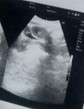

Assalamualaikum,bun saya mau tanya,dari bbrpa bulan yg lalu perut saya keram gitu kan,saya takut ada penyakit semacam apa gitu, karna udh hampir dua bulan tidak haid,akhir nya saya di rujuk ke usg abdomen buat penyakit dlm,tapi dokter usg nya bilang untuk dtng kontrol bsk ke dokter kandungan di rs sana nya,apakah keram lelah,mual, termasuk saya hamil bun,kembar kah?